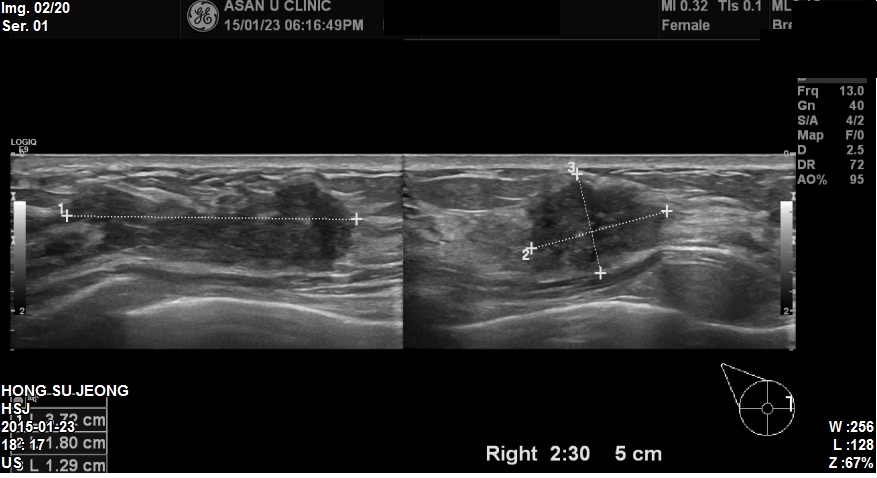

우측유방에 만져지는 멍우리로 내원하신 35세 환자분이십니다

본원에서 유방초음파시행후 우측 2:30방향에 3.7cm혹 조직검사 시행하였고

결과 침윤성 유관암진단되었습니다.